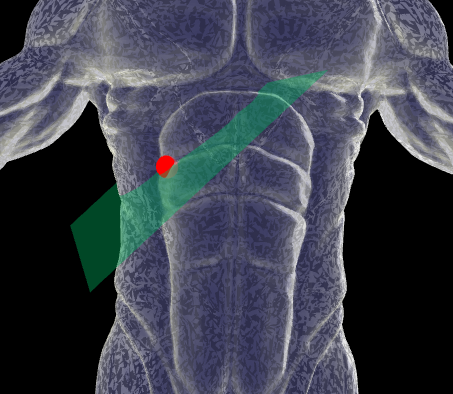

• Ubicación: Coloque el transductor debajo del arco costal derecho en sentido axial (horizontal).

• Inclinación: Incline el transductor hacia el lado craneal (hacia la cabeza) para obtener un ángulo óptimo.

Plano Referencia